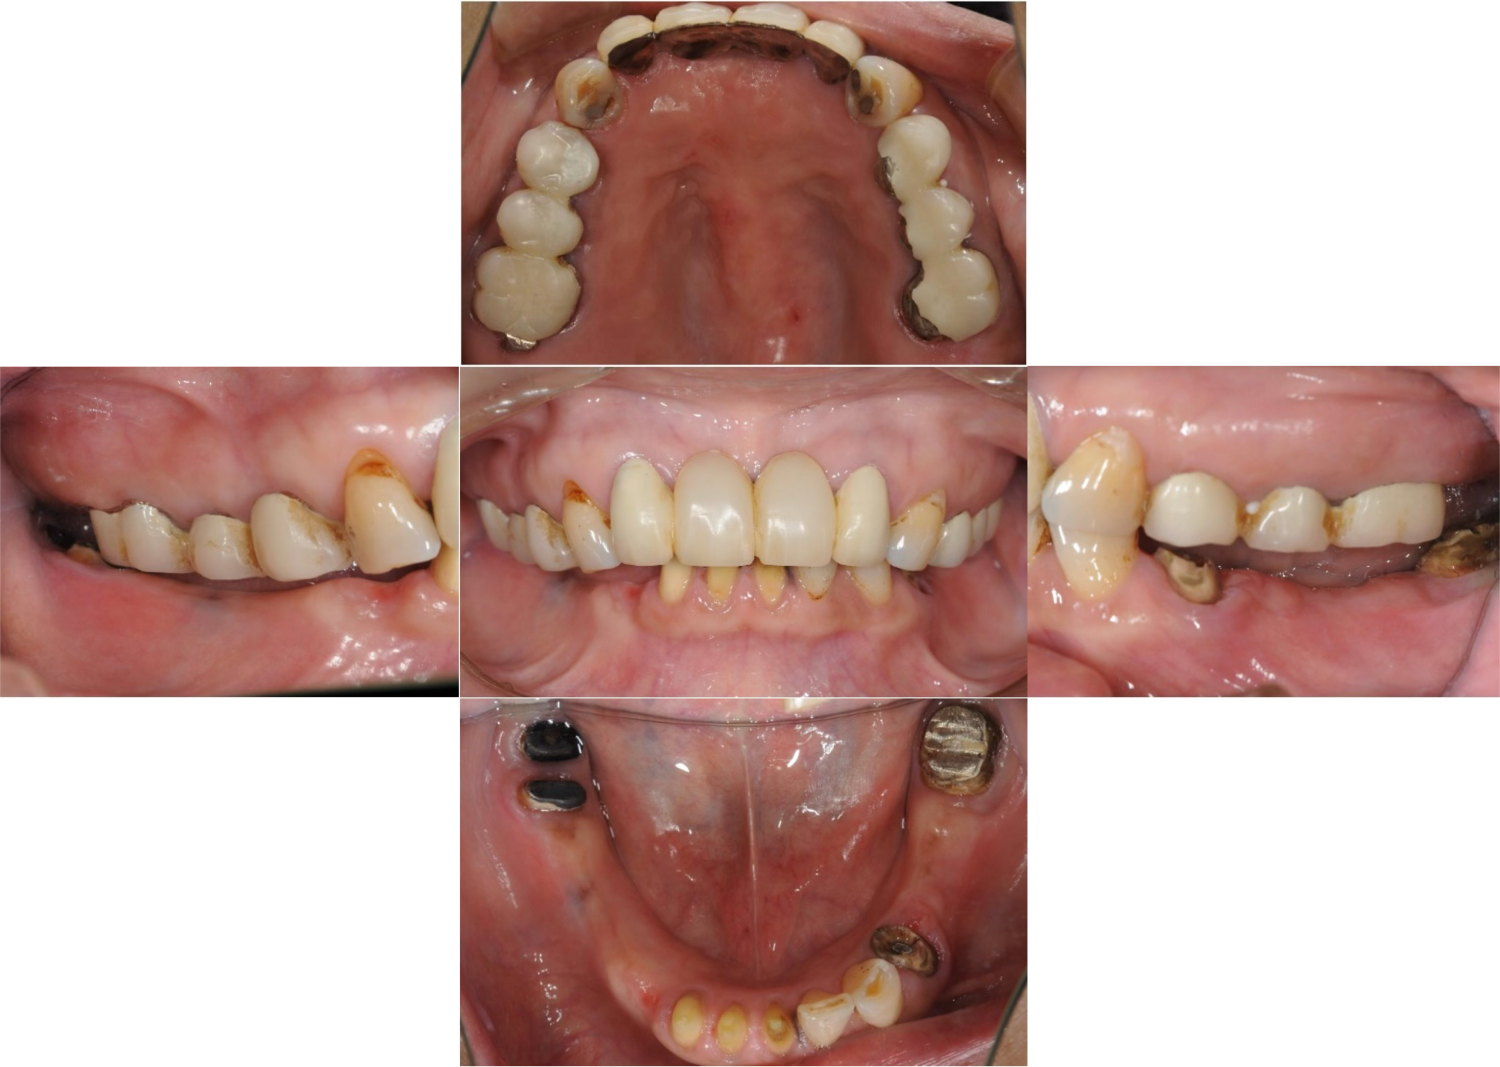

| 主訴 | 全顎治療希望、全顎的に歯が動く、奥の歯がなくて噛めない。できるだけ綺麗で噛めるようになりたい。 |

| 治療内容 | 全顎的に歯周病、前歯部の被蓋が深く、重度歯列不正が認められるため、 歯周外科を含む歯周治療、矯正治療、インプラント治療、セラミックによる補綴治療後メインテナンスに移行しました。 |

| 治療費 | 5,060,000円(税込)(インプラントすべて含む) |

| 治療期間 | 2年4ヶ月 |

| 治療回数 | 90回 |

| 想定されたリスク | 矯正治療の後戻り、歯周病の再発、食いしばり(パラファンクション)によるセラミックの破折、歯の破折のリスクがありました。 |